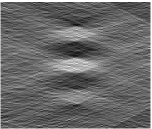

Finally, we show in Fig. 6 a region-of-interest (ROI) in the in-focus plane of a microcalcification (MC) cluster. The top row shows reconstructions from noiseless data, the bottom row shows reconstructions from noisy data. The entire cluster consists of 6 MC, with another triangular arrangement 6 mm below the one depicted. In the noiseless images, patterns caused by streaking artifacts can be perceived for the FBP and EM reconstructions. Image quality in the TV reconstruction is clearly superior in this situation.